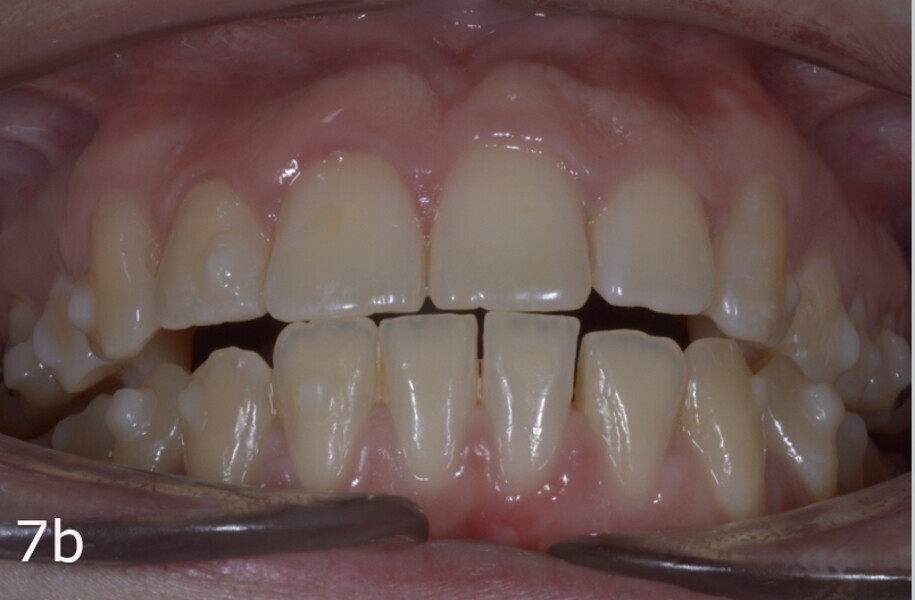

The treatment objectives included closing the anterior open bite, achieving a bilateral Angle Class I relationship and a proper overjet and overbite, correcting the midline discrepancies, and achieving a profile harmonisation. The treatment plan consisted of orthodontic camouflage treatment with asymmetric distalisation in three of the four quadrants using Invisalign aligners (Align Technology) and third molar extraction. The Invisalign Comprehensive package was chosen, and 63 pairs of aligners were used (Figs. 7–10). Each aligner was worn for 20 hours a day for one week each. The use of Class III elastics on both sides was indicated. Afterwards, ten refinement aligners were needed to improve the interdigitation on the right side (Figs. 11 & 12).